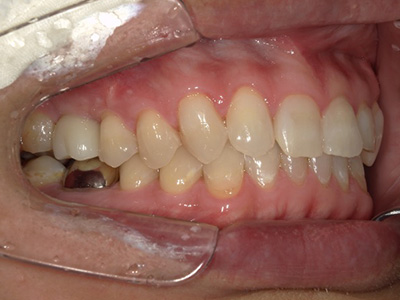

見た目も噛み心地も妥協しない

「補綴主導型インプラント」

一切妥協しないインプラント

最終的な被せ物(補綴)の理想的な形・位置から逆算し、インプラントを噛み心地と見た目に最適な位置に設計・埋入します。

技工士と院長が共同で設計し、その中心に正確にインプラントを配置。自然な見た目と快適な噛み心地の両立が可能になります。